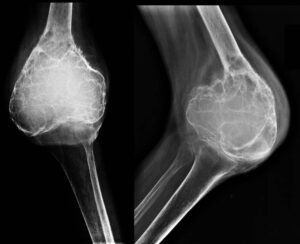

Vücuttaki kemik dokusunda anormal ve hücresel olarak kontrolsüz büyümeyle karakterize edilen bir tümör türüdür. Genellikle kemik ağrısı, şişlik ve kırıklar gibi semptomlara neden olabilir. Kemik tümörü, iyi huylu veya kötü huylu olabilir ve çeşitli faktörlere bağlı olarak gelişebilir. Tanı ve tedavi genellikle radyolojik görüntüleme, biyopsi ve cerrahi müdahale gerektirir.

Kemik Tümörü BelirtileriÇoğu cerrahi olarak çıkarılabilir. Cerrahi, tümörün tamamen çıkarılmasını ve sağlıklı doku bırakılmasını amaçlar. Kemik koruyucu cerrahi, tümörü çıkarmak için mümkün olduğunca sağlam kemik dokusunu korumaya yöneliktir. Ancak, bazen tümörün büyüklüğü veya konumu nedeniyle kemik alınabilir ve yeniden yapılandırma gerekebilir. Radyoterapi, yüksek enerjili ışınlar kullanarak kanser hücrelerini yok etmeyi amaçlar.